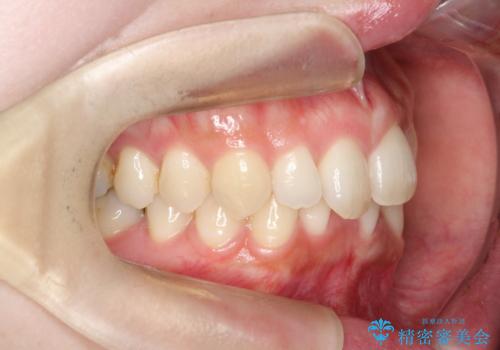

- 患者様は、上下前歯の歯列不正(ガタガタ)を主訴としてご来院されました。治療計画として、透明なマウスピース型矯正装置「インビザライン」を使用し、約2年の期間を見込んで前歯部の歯列を整える方針を立てました。特に下顎前歯に歯肉退縮のリスクがあるため、治療中にIPR(インタープロキシマルリダクション)を行い、歯間を適切に削ることで、過度な圧力を避け、歯肉退縮を防ぎながら配列を進めました。治療は慎重に進め、最終的にきれいで整った前歯の歯並びを目指しました。

インビザラインによる矯正治療は、患者様自身が装着するマウスピース型の装置を使用するため、装着時間の徹底が重要です。特に、下顎前歯の歯肉退縮を避けるため、IPRを施すことで歯間スペースを確保し、歯肉にかかる負担を減らしました。この方法により、歯並びを整えながらも歯肉の健康を保つことができます。治療期間中は定期的にチェックを行い、歯肉の状態や歯の動きを慎重に確認しました。また、治療後はリテーナーを装着して歯並びを維持し、安定させました。